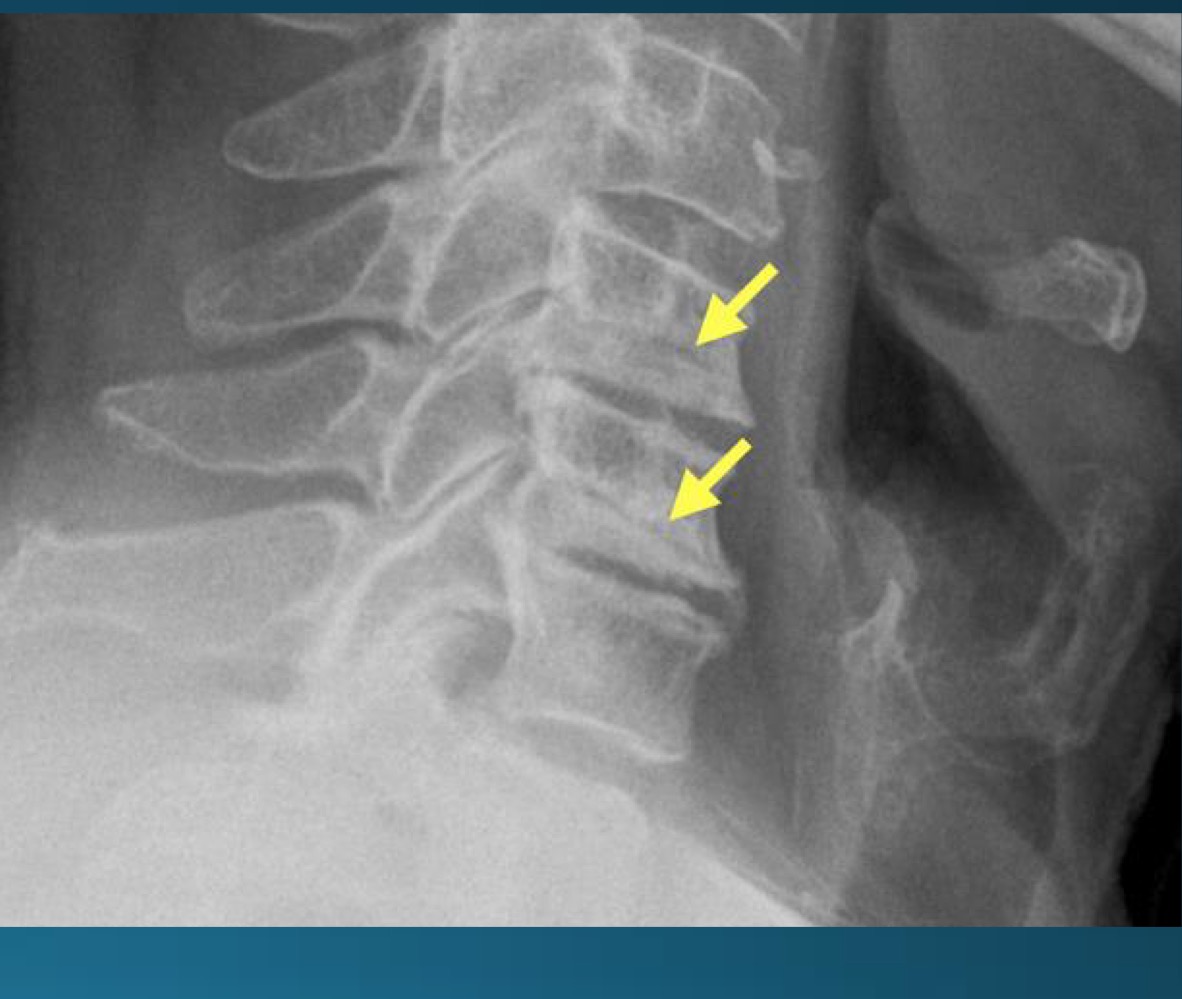

what are the findings in this image?

facet arthrosis